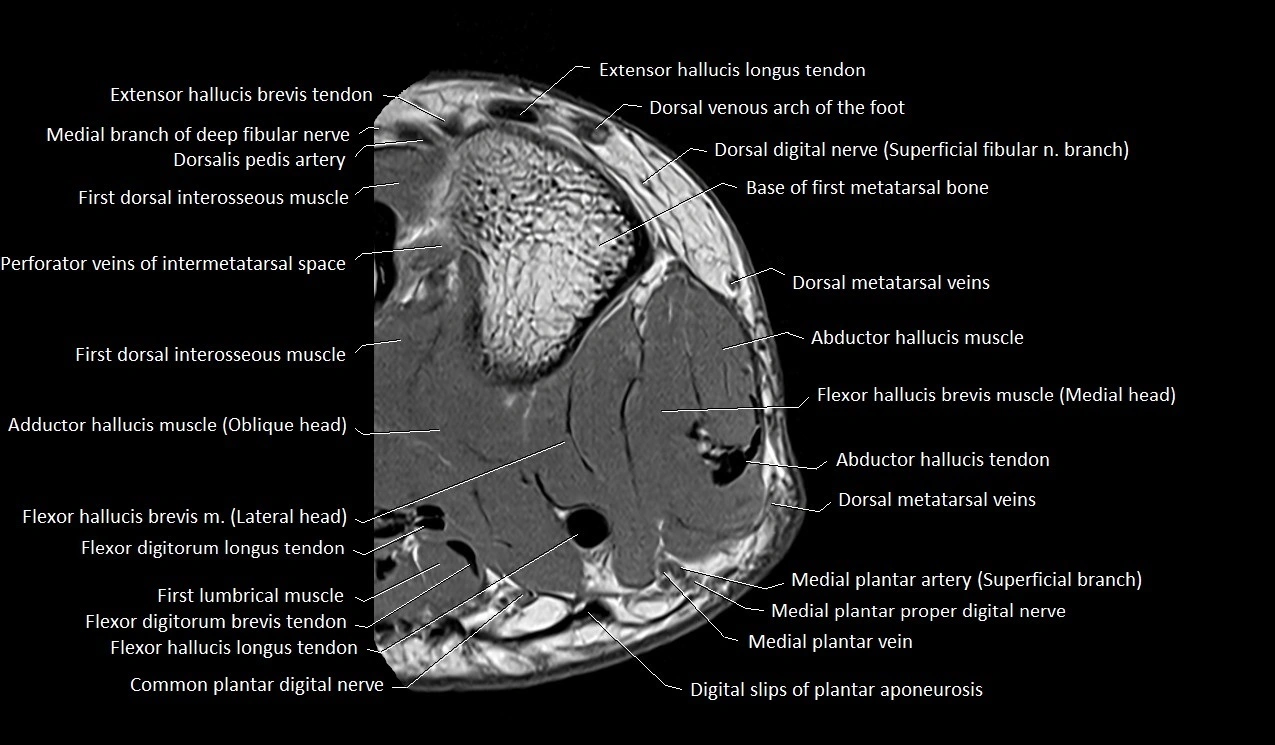

MRI image

image